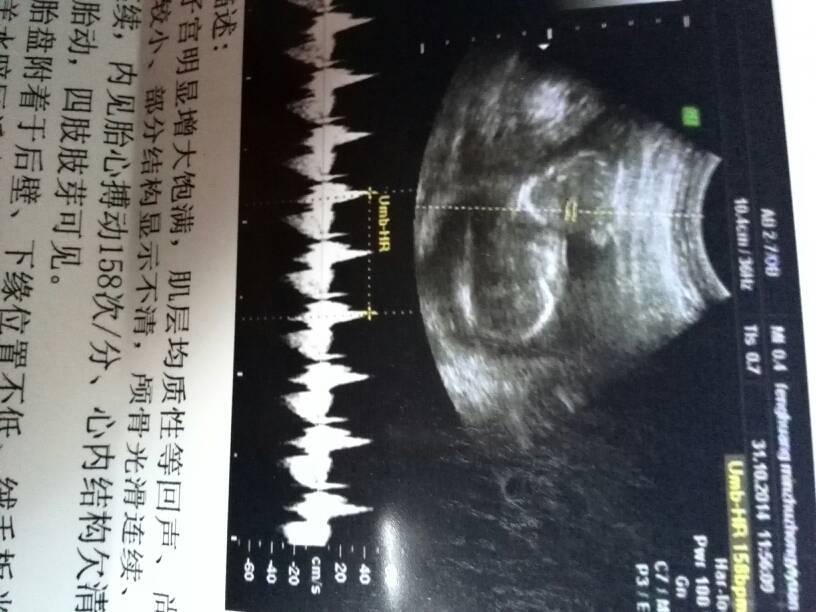

宝妈,看这个单子是看不出来的,可以去做b超,医生看得出来

单子看不出来,必须照b超才能知道男女,但现在医生不会告诉你性别的